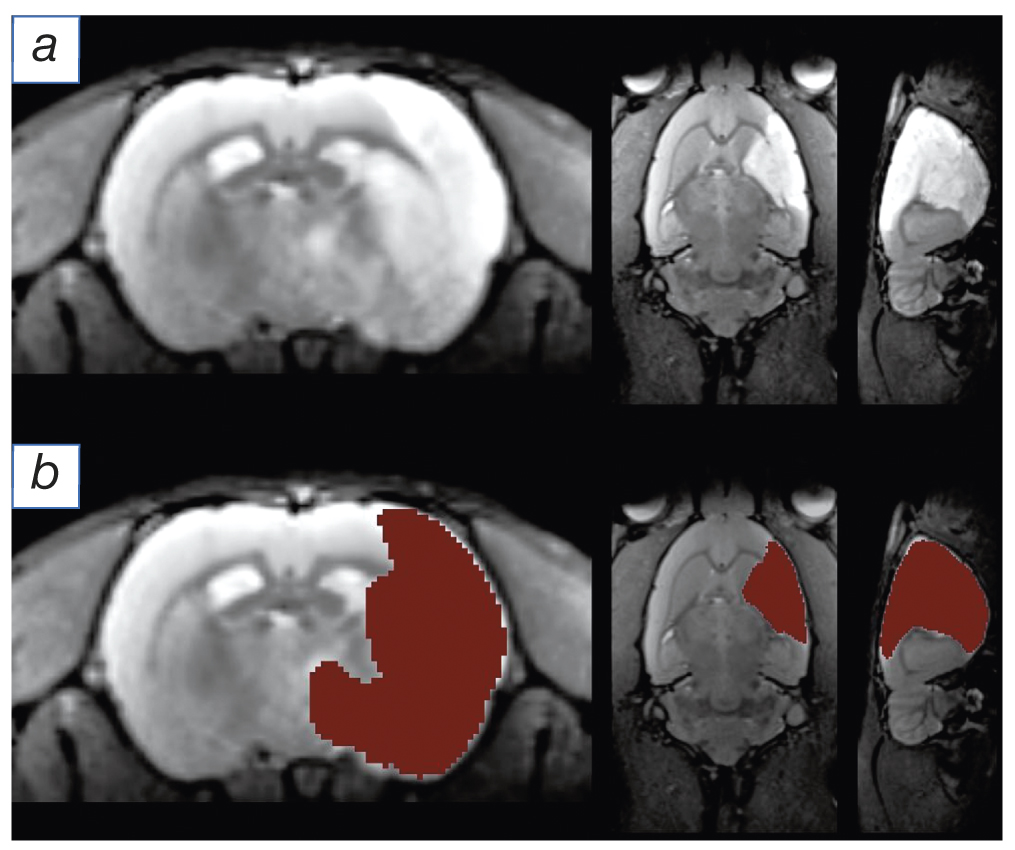

Fig. 1. An example of cerebral infarction segmentation using artificial intelligence: a — T2-weighted images in the axial, frontal and sagittal planes (from left to right), in which a hyperintense lesion of cerebral infarction is visualized in the right hemisphere; b — automatic segmentation of the lesion of cerebral infarction (marked in red).

In order to compile an atlas of the blood supply systems of the intracranial branches of the internal carotid artery according to MRI data, we have used an artificial intelligence system, allowing for significant segmenting the cerebral infarction zone after the occlusion of the medial cerebral artery (Fig. 1). The obtained results of segmenting the experimental cerebral infarction were registered in a unified coordinate space using the rat brain template (Fig. 2, a). Based on the obtained segmentation files, summarized in a single coordinate system, the thermal maps of the rates of developing the cerebral infarction foci were compiled (see Fig. 2, b).